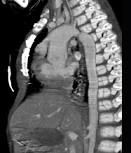

问题 患者,男性,8岁,发绀、气促,易感冒,彩超提示只见一个心室,CT检查如图所示,请选择正确的选项 ( )

选项 A、最常并发肺动脉瓣及瓣下畸形 B、可伴有内脏心房异位、房间隔缺损、共同心房、双上腔静脉等发育畸形 C、为一种较为复杂的先天性疾病 D、以前诊断主要依靠心血管造影 E、考虑为单心室共同动脉干

答案 ABCDE